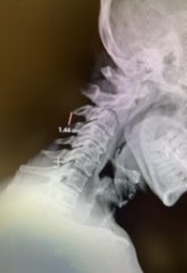

(3) Post operative AP and lateral cervical x-ray demonstrating good placement of hardware and alignment.

Patient did well from surgery with reduced pain in left shoulder and no further leak.(Fig. 3)